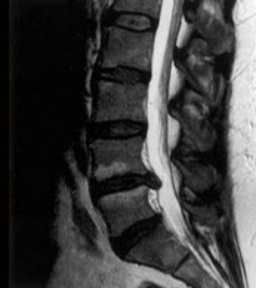

1、如图所示,低位腰麻是指阻滞平面在()

A.T10以下

B.T4以下

C.T6以下

D.T12以下

E.T8以下

正确答案:T10以下

5、临床上常将感觉阻滞平面超过T4者称高位脊麻,T10平面以下者称低位脊麻。